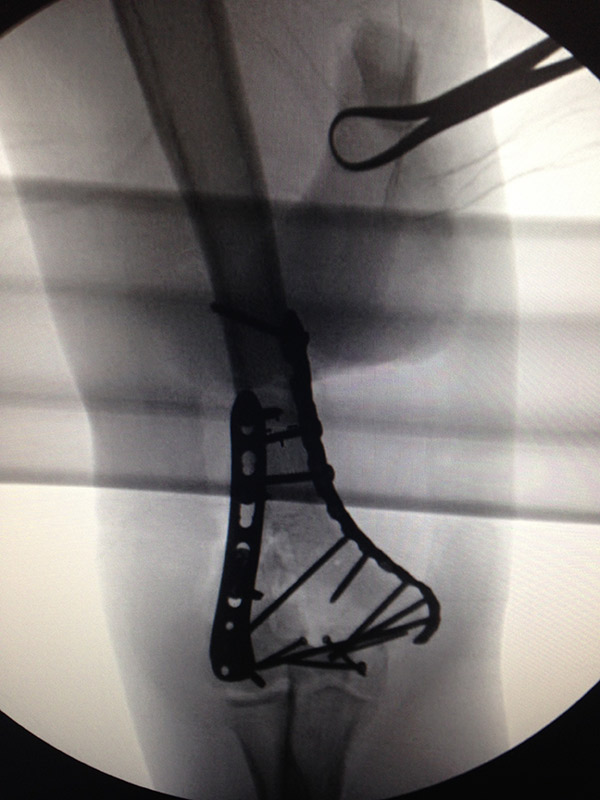

X IS FOR X-RAY

Here’s my titanium elbow for a laugh.

I broke my hand, my shoulder, my elbow and my face but the real injury this year was to my Irish pride as it was discovered that under my tracksuit I was wearing yellow and black Lycra cycling shorts. Yes, LYCRA. This is not very rock ‘n’ roll.

Recovery has been more difficult than I thought… As I write this, it is not clear that I will ever play guitar again. The band have reminded me that neither they nor Western civilization are depending on this.

I personally would very much miss fingering the frets of my green Irish falcon or my (RED) Gretsch. Just for the pleasure, aside from writing tunes. But then does the Edge, or Jimmy Page, or any guitarist you know have a titanium elbow, as I do now? I’m all elbows, I am.